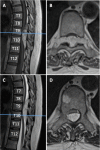

Results: A 65-year old female presented with neurogenic claudication and magnetic resonance imaging (MRI) revealed lumbar spinal stenosis. Following decompressive surgery, she experienced symptom resolution, but three months postoperatively she presented to the emergency department with acute paraparesis. A thoracic MRI revealed a lesion located between T8 and T10 causing severe spinal cord compression. Following emergent laminectomy and en bloc resection, the patient regained function and the lesion was diagnosed as SAL. Our literature review revealed 178 reported cases, with a female and thoracic predominance. The majority of patients underwent surgical treatment, achieving a gross total resection in most cases. Similarly, complete symptom resolution was the most common outcome.